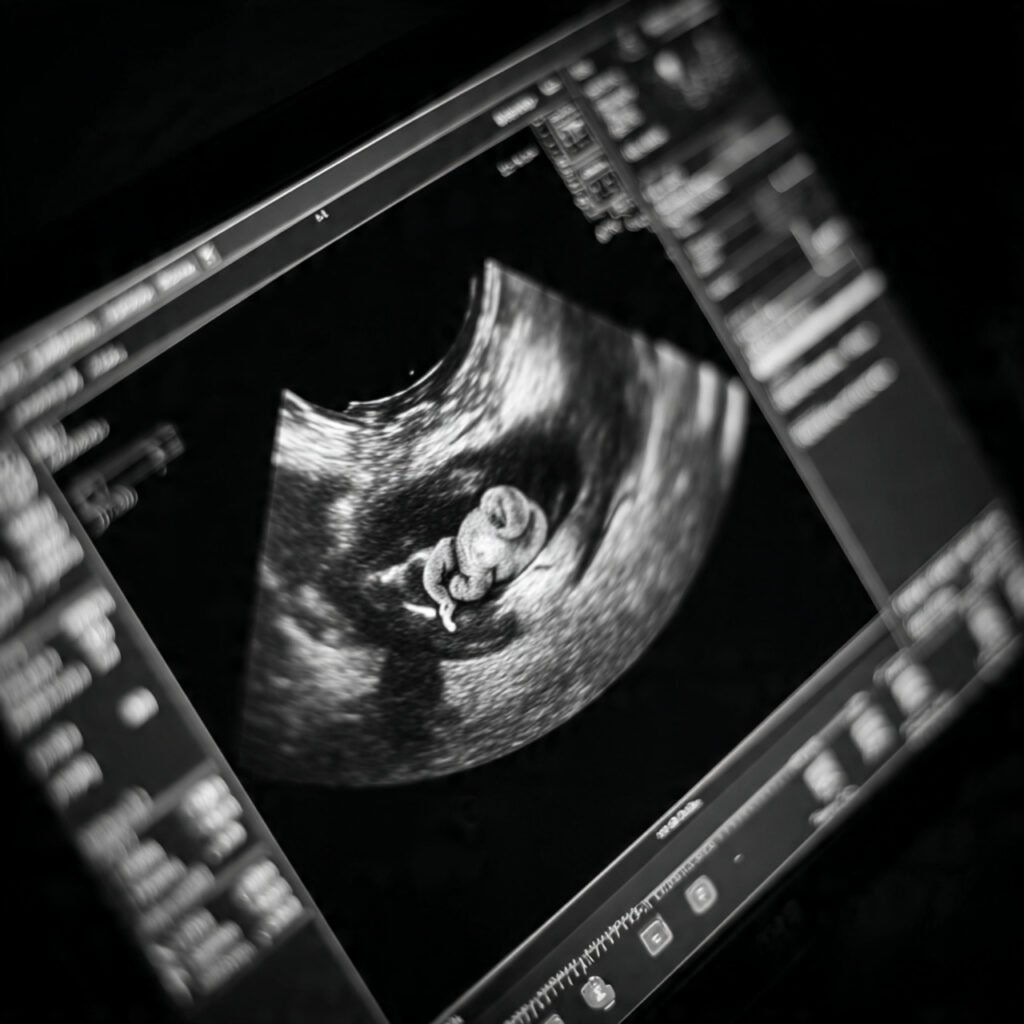

Founder of Nisarga Diagnostics, is a renowned fetal ultrasound specialist with over 20 years of expertise. An alumnus of Government Medical Colleges in Mysore and Bangalore, he also holds a D.N.B. from the National Board of Examinations, Delhi, and certification from the Fetal Medicine Foundation, London. A former Professor and HOD, he has trained countless PG students and junior radiologists, shaping the future of fetal imaging in India.